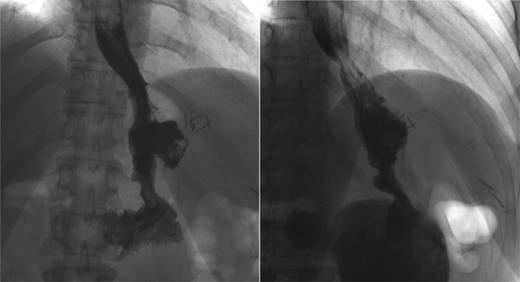

Three months later, patient presented with recurrent abdominal wall abscess. A GS demonstrated ongoing leak from the GCF (Fig. 2). On 8 September 2014, she underwent a laparoscopic fistulectomy. The fistula tract was transected and the gastric part of fistula excised. The spleen was involved in the inflammatory cavity, but splenectomy was eventually avoided. Since the gastric sleeve was healthy, it was decided not to resect the remaining stomach. No evidence of a fistula was detected on a GS performed at the 6-week postoperative check (Fig. 3).

Persistent leak detected with GS. The images clearly show persistence of the leak along with the fistula tract. One of the endoscopic clips previously positioned is also visible.